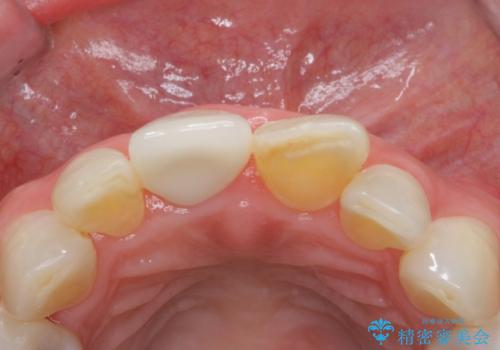

転んで前歯を折った 歯を抜かない治療

- 転んで前歯が折れたとのことで来院されました。

検査の結果、歯は大きく折れておらず、骨の中に埋め込まれていた状態であったため、部分矯正で歯を引っ張り出していきます。

ぶつけて埋まってしまった歯は、場合によって矯正治療で引っ張り出すことで保存することができます。

今回は歯の神経が死んでしまっていたため、根管治療後に被せ物を装着して見た目の綺麗さを回復しました。